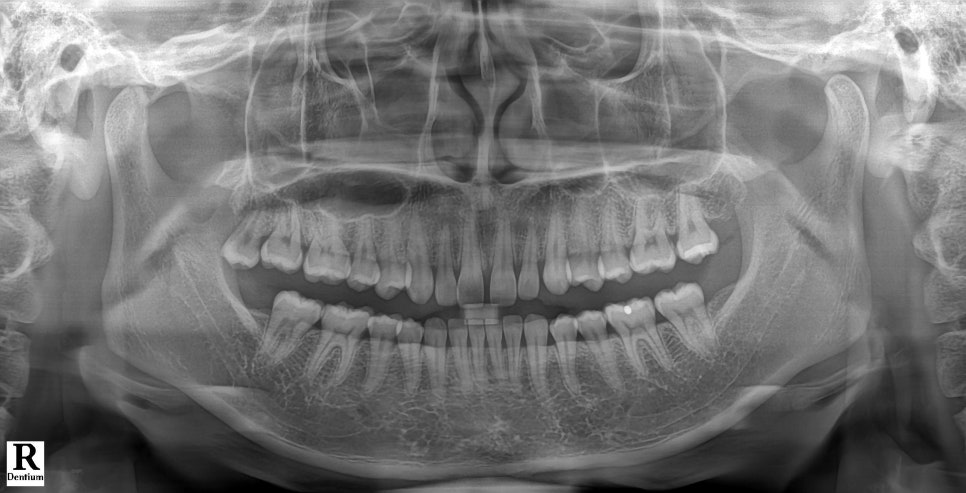

촬영일 : 251121

전체적인 상태를 보기 위해 엑스레이를 촬영했고, 다른 문제는 없다는 걸 확인했어요.